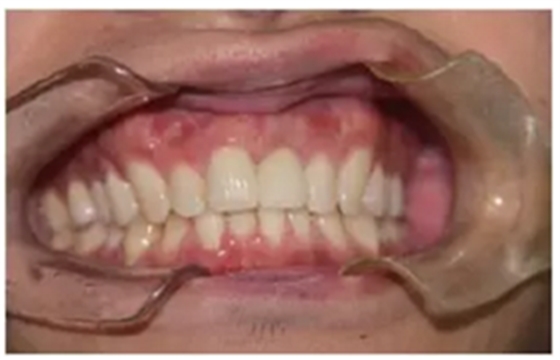

永久修復(fù)

永久修復(fù)后3年進(jìn)行回訪,種植體骨結(jié)合穩(wěn)定,美學(xué)效果良好。

圖14 永久修復(fù)3年后的回訪